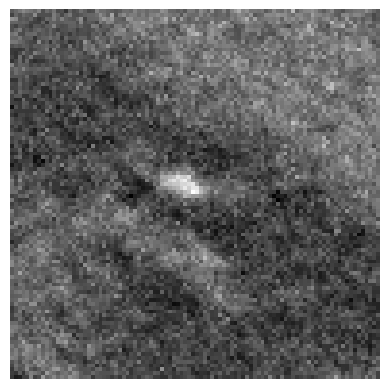

The effectiveness of our label-guided approach is visualized in Figure 4, which compares feature representations generated by standard DINO and DINO-LG models via PCA analysis. The figure shows an original CT slice containing coronary calcification in the left anterior descending artery (a), where the ground truth annotation (b) occupies approximately 0.04% of the image area. Standard DINO features (c) exhibit diffuse activation across cardiac structures, while DINO-LG features (d) demonstrate concentrated activation on calcified regions (bright yellow areas), validating successful feature guidance toward regions of clinical interest. The PCA visualization is applied to 768-dimensional [CLS] token embeddings extracted from the final transformer layer to illustrate how label-guided training directs the model’s attention to task-relevant features.

Refer to caption

(a)

(b)

(c)

(d)

Figure 4: Feature visualization comparison via PCA. (a) Original CT slice. (b) Ground truth annotation. (c) Standard DINO features. (d) DINO-LG features.